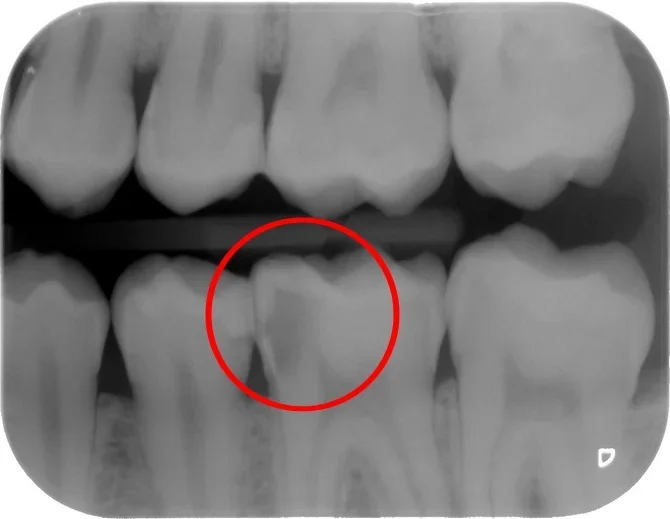

La terapia della carie dentale viene attuata con otturazioni, ricostruzioni dirette o indirette (intarsi) in resina composita o ceramica. Le tecniche conservative permettono inoltre correzioni estetiche anche su denti sani senza bisogno di protesi.